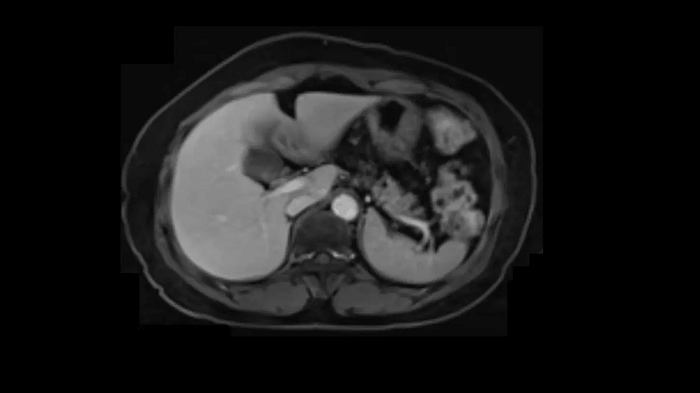

Abdominal imaging

Abdominal imaging with the new Contour 24 coil

Increased patient comfort with ultra-high-density coils that provide a blanket-like feeling.

3D T1 CAIPIRINHA VIBE Dixon

1 station

50 cm z-FOV

Full abdominal coverage from the liver dome to the pelvis enables comprehensive oncological scans in a single station with outstanding quality.

- Body 18

- BioMatrix Spine 72

Image Credit: Siemens Healthineers